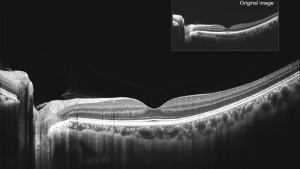

Чудова якість ОКТ-зображень з усередненням 100 зображень

Mocean 4000 робить 100 зображень менш ніж за одну секунду і об'єднує їх разом для створення зображення високої чіткості з мінімізованим шумом зернистості

Осьова оптична роздільна здатність 5 мкм (цифрова - 3 мкм)

ОКТ-зображення з високою роздільною здатністю виявляє приховані патологічні зміни